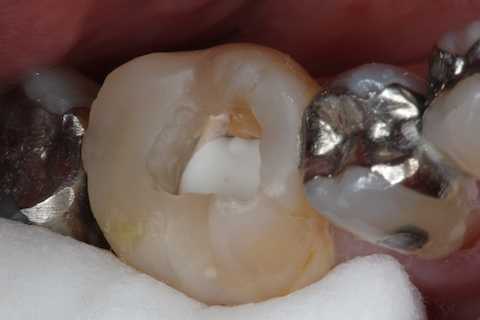

残根上のCR8 2025.10.28